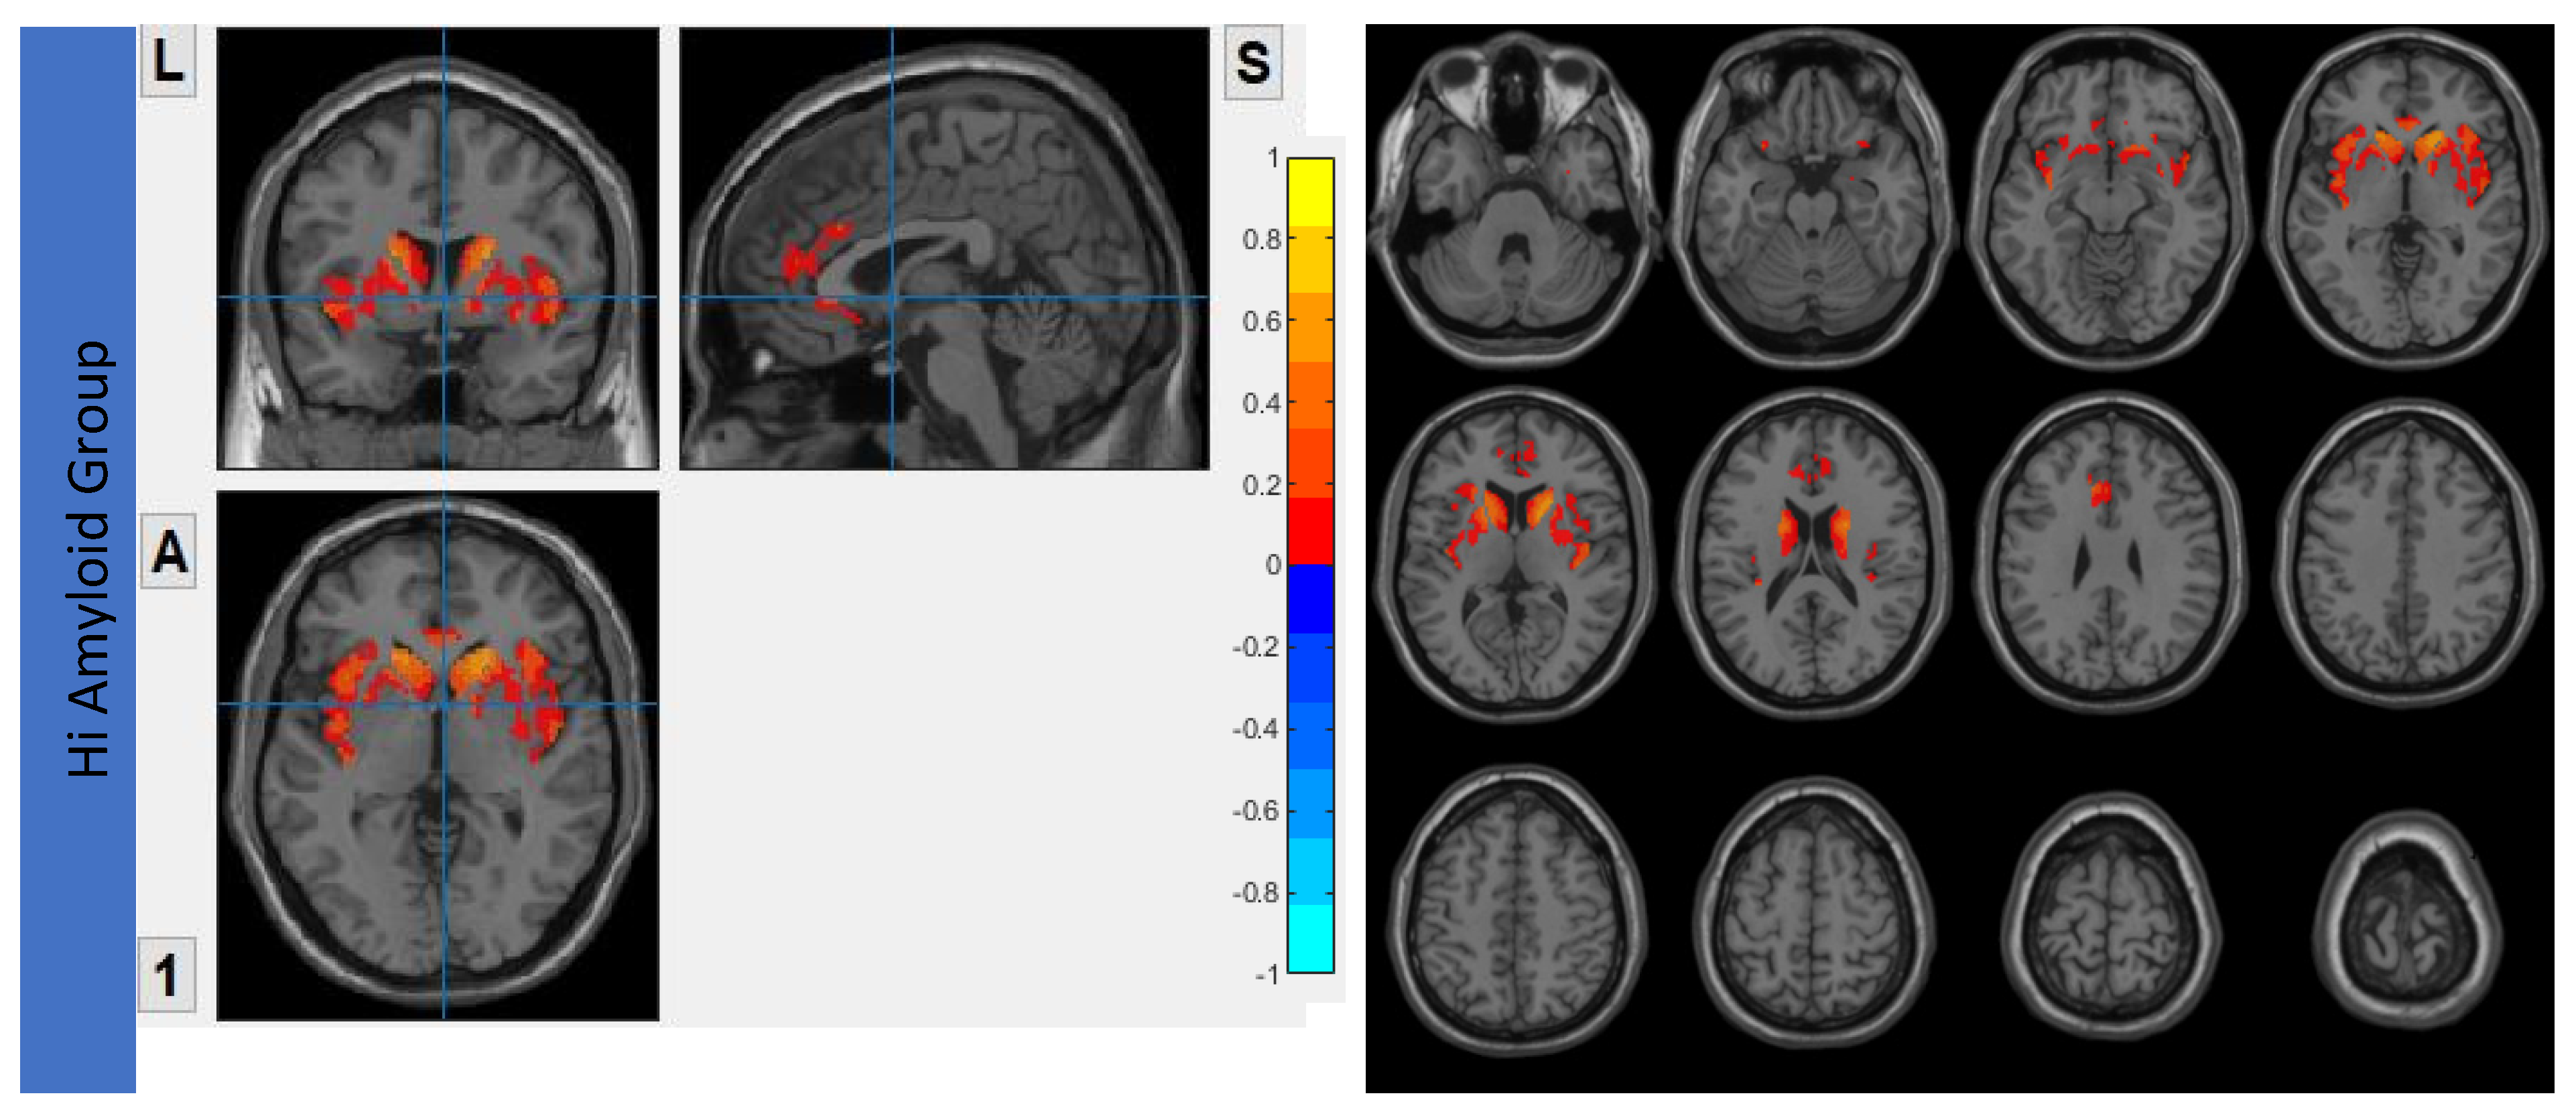

7.2. Within CEN